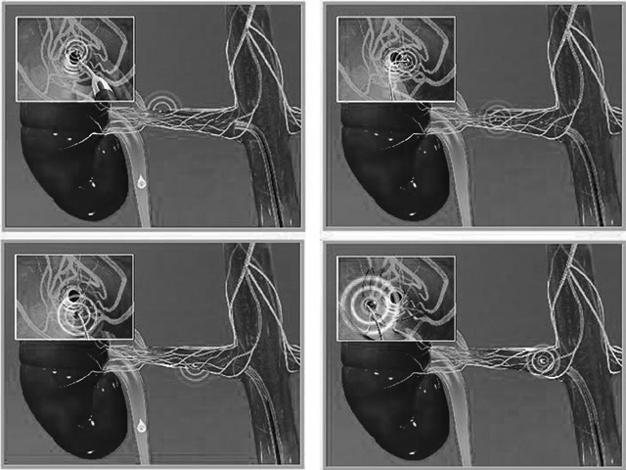

В 1989 году группа немецких исследователей во главе с Хартмутом Кирхгаймом опубликовала результаты эксперимента на животных, в котором симпатические нервы, идущие к почке, вывели из строя с помощью электрических импульсов. Эта «блокировка» привела к желаемому результату: производство ренина упало — и гипертония исчезла. При этом серьезных побочных эффектов лечения, таких, как раньше, не наблюдали. Исследователи сразу же подумали о возможности использовать этот метод для борьбы с гипертонией у людей. Понадобилось еще несколько десятилетий, чтобы довести технологию до ума и создать специальный катетер с миниатюрным передатчиком низкочастотных радиоволн, действующим по специальному алгоритму. Он вводится в почечную артерию пациента для того, чтобы воздействовать на нервные волокна, находящиеся рядом с сосудом с внешней стороны. Сегодня это уже не называют операцией — бескровную процедуру выполняет интервенционный кардиолог.

В 2007 году новый метод впервые применили для лечения нескольких австралийских пациентов, страдавших злокачественной гипертонией. Гейл Лендер, одна из первых пациенток, сегодня вспоминает, что ей было очень больно, ведь обычные методы анестезии при этой процедуре не действуют. Но именно благодаря новому методу Гейл сейчас живет полноценной жизнью без ежедневной горсти таблеток — она принимает лишь два лекарства, чтобы стабилизировать давление. Ее примеру за несколько лет последовали уже пять тысяч человек — пока в основном в рамках клинических исследований и коммерческой медицины.